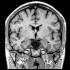

Légende de coupe coronale

Légende d'une autre coupe para-sagittale

Légende des coupes para-sagittales

Légende du centre de l'encéphale

Légende - coupe sagittale

Légende de l'encéphale

Coupe d'encéphale